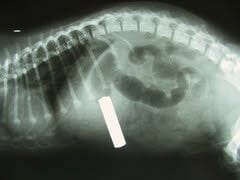

Si se tragara la pila y esta permanece ahí puede haber una toxicosis crónica. Lo mejor es un seguimiento radiográfico del cuerpo extraño para ver si va avanzando y es expulsada con las heces. De no ser así, pues una laparatomía para su remoción.

No quiero inquietar, pero ¿Y si no nos enteramos que no se la tragó? Quien tenga fuertes sospechas, pues una radiografía nos sacaría de dudas, se ve claramente en la misma.